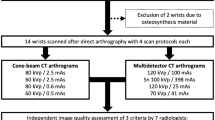

Joint phantoms and 10 human cadaveric wrist and elbow joints were scanned with C-arm FPCT (5-s, 8-s, and 20-s runs) and standard MDCT using different and optimal concentrations of iodinated contrast material. CT numbers of contrast material, tissue, and noise were measured and contrast-to-noise ratios (CNR) calculated for quantitative analysis. Image and depiction of cartilage, bone, and soft tissues were rated. Radiation doses were compared.

Flat-panel CT acquisitions

Flat-panel CT acquisitions were performed on an angiographic unit (Artis Zeego multi-axis system, Siemens Healthcare, Forchheim, Germany) with a C-arm-mounted FP detector. The FP detector (30 × 38 cm) was operated in a standard 2 × 2 binning mode where four neighboring detector pixels, each of 154 μm size, are read out together to allow an increase in the number of frames that can be read out per second.

Similar to the recent feasibility study of Guggenberger et al. [24], three different imaging protocols for FPCT were used. Protocols mainly differed in total scan duration: 5, 8 and 20 s, respectively. For the 5-s and the 20-s runs vendor-specific default pre-settings were used. They were originally designed by the vendor for abdominal and neurovascular interventional applications respectively. The 8-s run, however, was custom-made to imitate the intermediate protocol used in the aforementioned feasibility study [24]. This intermediate protocol was originally designed as a trade-off between the 5-s and the 20-s run with respect to scan duration and radiation dose.

The 5-s, 8-s, and 20-s runs had different angulation steps (1.5°, 0.5° and 0.4° respectively), which resulted in three different numbers of projections (133, 400, and 500 respectively) as well as different scan durations for the standard 200° rotation of the C-arm around the object. Other scan parameters were: tube voltage, 70 kV; distance from the source to the axis of rotation, 78.5 cm; distance from the source to the image plane, 120 cm. Collimation of the field-of-view of FPCT was kept constant for all scans. The angiography unit automatically calculated the tube current–time product as well as the dose–area product (DAP in μGym2), which are parameters for the radiation dose.

Multidetector CT acquisitions

A 64-section CT unit (Definition AS, Siemens Healthcare, Forchheim, Germany) was used for MDCT employing the standard clinical protocol, which is usually used for CT arthrography of the wrist and elbow at our department. The protocols include use of automated attenuation-based tube–current modulation (CAREDose4D, Siemens) and the z-flying focal spot technique. The detector collimation was 16 × 0.3 mm. Other scan parameters were: tube voltage, 120 kV; tube current–time product per rotation, 120 mAs; pitch, 0.85. After each study, the scanner generates automatically a “patient” protocol from which the computed tomography dose index (CTDIvol in mGy) and the dose–length product (DLP in mGy.cm) were recorded as parameters for the radiation dose.